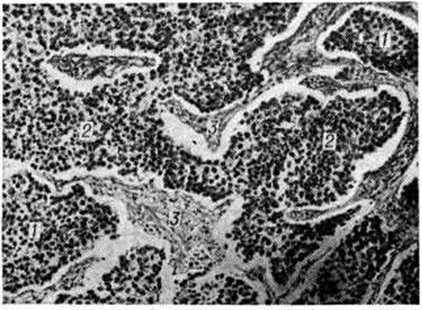

Микроскопически Дисгерминома состоит из крупных круглых или полигональных клеток с большими ядрами, содержащих гликоген и образующих ячейки и поля, разграниченные соединительнотканными прослойками, которые обильно инфильтрированы лимфоцитами (рисунок). Иногда видны многоядерные гигантские клетки типа Пирогова — Лангханса. Цитоплазма клеток Дисгерминома содержит щелочную фосфатазу. Опухоль рано метастазирует по лимфатический, и кровеносным сосудам. Морфологически Дисгерминома идентична атипическим тератомам эпифиза мозга (шишковидного тела) и гипоталамуса.